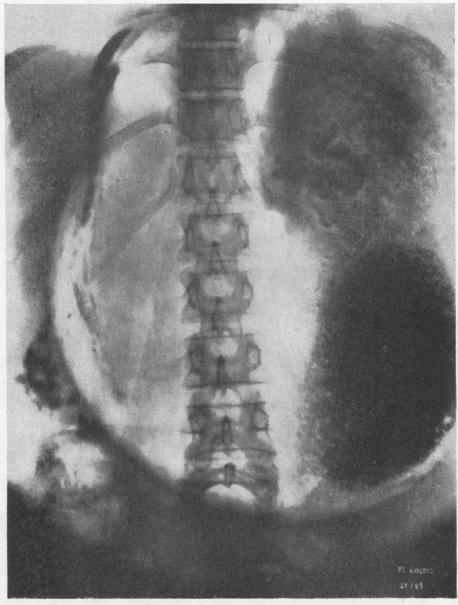

Fifty-seven cases of diaphragmatic hernia and eventration.

Thorax. 1950 Dec;5(4):343-61. doi: 10.1136/thx.5.4.343.